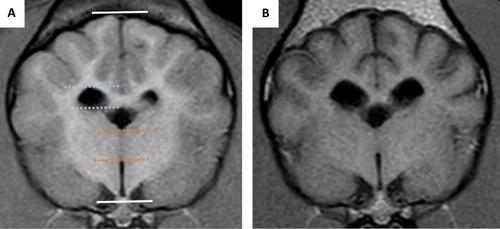

Retrospective study. Interthalamic adhesion thickness to brain height ratio (ITr), lateral ventricle to brain height ratio (LVr), interthalamic adhesion thickness/brain height to lateral ventricle/brain height (ITr/LVr), bicaudate ratio (BCR) and total parenchymal brain volume (TPBV) were measured on both MRI studies and compared.

Thirteen dogs relapsed and four died during the study period. Median time between MRIs was 12 months, and only one imaging study (1/23) was considered normal on the second scan. All MRI variables measured significantly changed between imaging studies, but only higher TPBV was associated with increased survival (OR = 1.59, CI = 1.006–2.51, p = 0.047); no variables were found to be associated with relapse. New lesions were identified in six dogs (four of which also showed contrast enhancing lesions), with 5/6 of these dogs subsequently relapsing.